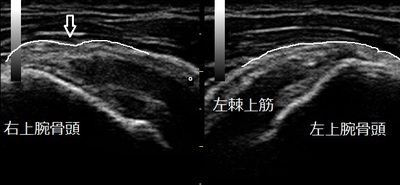

右肩(患部) 左肩(正常側)

右肩前方の上腕骨頭を押さえるととても痛みます。手のひらを下にして腕を挙げようとすると痛くて出来ません。超音波検査で棘上筋の一部が、正常側と比較して不整になり凹んで損傷していました(左画像の矢印)。凹んだ腱を修復させ、痛みを軽減させる理学療法を行います。

肩峰下インピンジメント症候群は、うでの上げ下ろしの時に棘上筋腱、棘下筋腱(腱板)が肩峰の下を通過します。肩峰と腱板の間には肩峰下滑液包があって、肩峰と腱板の摩擦や衝撃を和らげているが頻回の挙上動作により腱板や肩峰下滑液包の炎症を引き起こしたり、さらには腱板の断裂などの損傷を引き起こすことがあります。